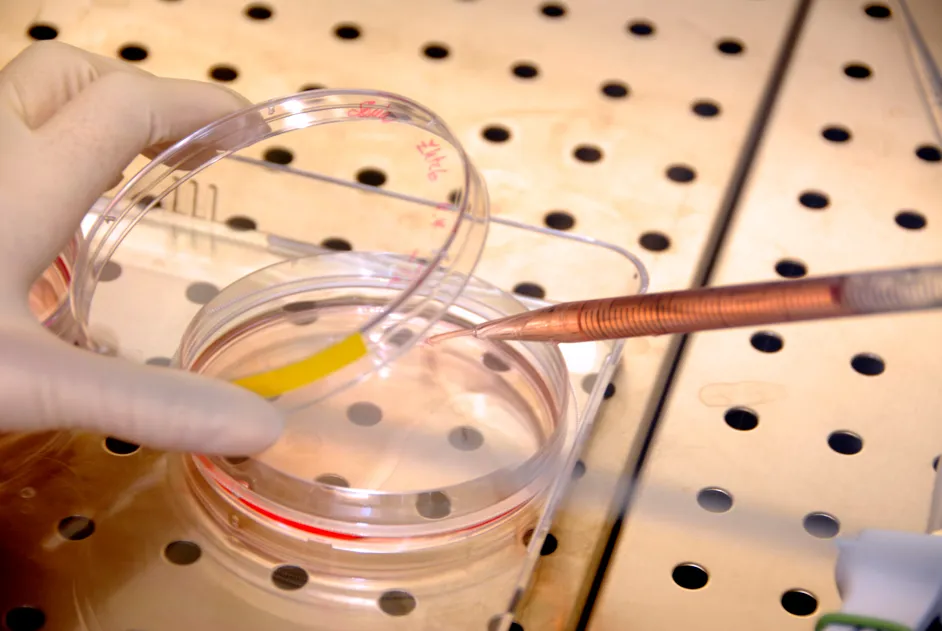

Du 4 au 30 novembre, l’AFM-Téléthon et l’Association des professeurs de biologie et de géologie (APBG) s’associent pour faire entrer le monde de la recherche dans les collèges et lycées. Les élèves vont ainsi pouvoir découvrir les dernières avancées de la recherche biomédicale et le quotidien d’un chercheur !

Du 4 au 30 novembre, l’AFM-Téléthon et l’Association des professeurs de biologie et de géologie (APBG) s’associent pour faire entrer la recherche dans les collèges et lycées.